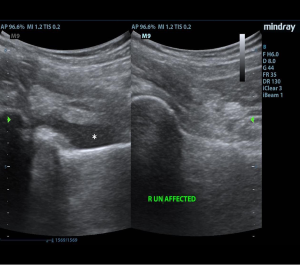

Initial ED course involved IV hydration, analgesia, and labs demonstrating ongoing leukocytosis with left shift, normal coagulation studies, and normal liver and renal function. Urine was sent for N. Gonorrhoeae and C. Trachomatis nucleic acid amplification tests. POCUS examination of bilateral hips revealed a 10 mm fluid collection anterior to the left femoral neck consistent with a hip effusion. Orthopedic surgery was consulted and requested an arthrocentesis, a procedure typically performed by an IR team at this institution, requiring time for transport, team organization, and room set-up. The EM team therefore elected to perform a POCUS-guided arthrocentesis.

With a linear array transducer positioned transversely over the inguinal region, the location of the femoral neurovascular bundle was marked using a surgical pen. The transducer was then rotated into a sagittal oblique position to visualize the hip effusion, and depth was measured to determine appropriate needle length. A low-frequency curvilinear probe was also briefly used to optimize visualization and to compare bilateral hips (Figures 1 and 2).